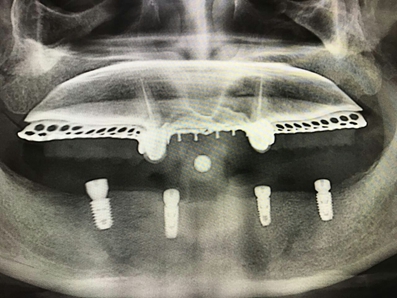

毛國斌種植病例——群討論分享